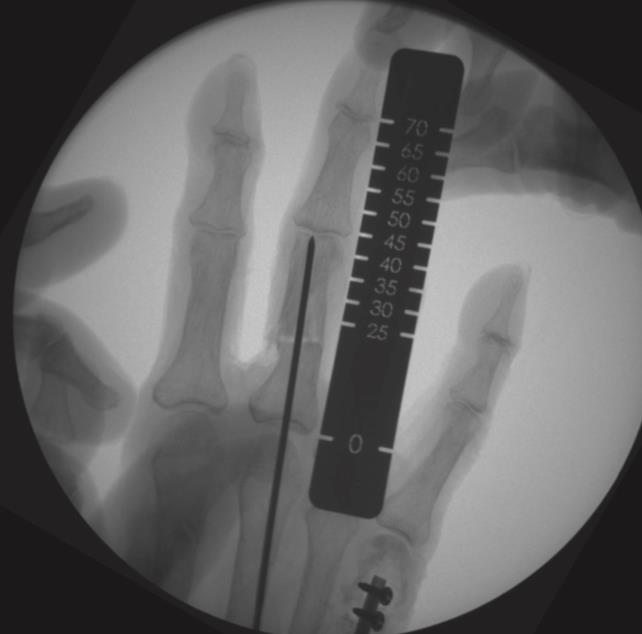

• insert a 1.6mm k-wire into the metacarpal head and advance it to the fracture site

• reduce the fracture under fluoroscopy and advance the k-wire into the metacarpal base

• determine nail length with a measurement ruler or depth gauge and subtract 10mm from the length reading

• for the antegrade approach, flex the wrist while advancing the k-wire through the base of the metacarpal until visible